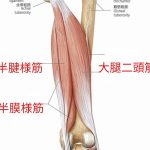

【陸上】ハムストリングス肉離れの発生局面

こんにちは。所沢接骨院の伝法です。 様々なスポーツで肉離れの危険は伴いますが、 全肉離れのなかでハムストリングスが一番多いと言われています。 ちなみに次に多いのは大腿四頭筋です。 今回は陸上短距離走でのハムストリングス肉離れについて少し触れます。 まず、ハムストリングスの肉離れの中でも 肉離れの発生局面からスプリント型と伸展型に分けられます。 スプリント型 ……続きを読む